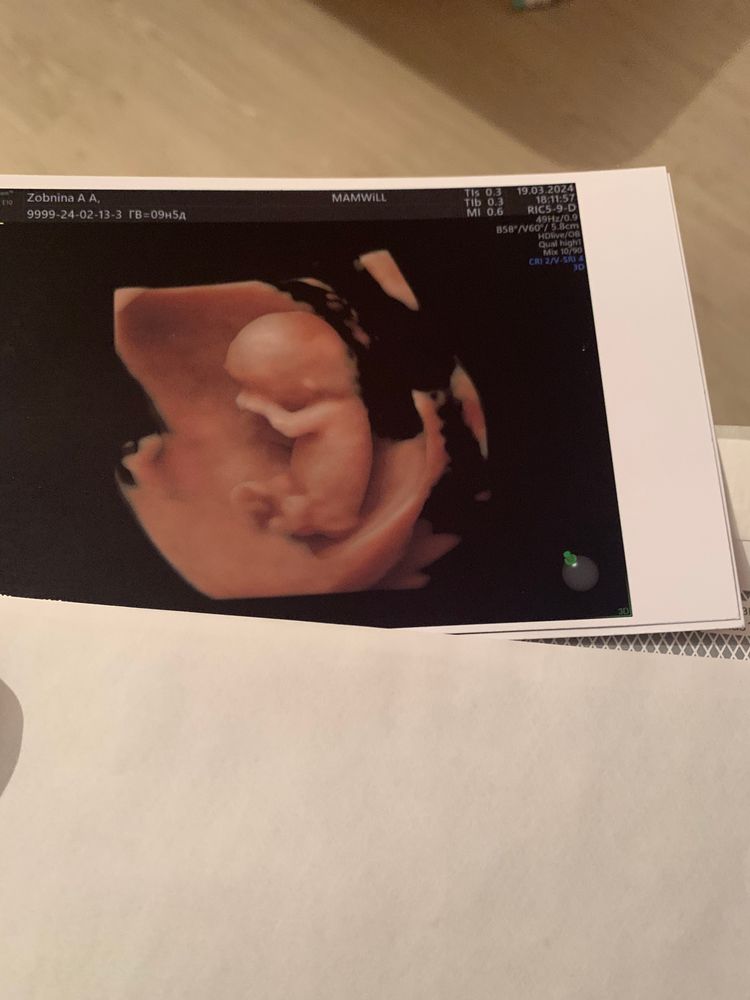

Здравствуйте. Прикреплю Вам свой предыдущий пост, как сходила на узи в 9 недель (1 фото) Ходила на узи в 9,5 недель. В итоге ( фото 2) Мне кажется, или я всё таки вижу увеличенное воротниковое пространство в зоне головы / шеи? Узист, увидела, что я переживаю и измерила твп, сказала, что 1,5 и это норма на данном этапе. Но, мне показалось или же я видела в конце, что она смерила ещё раз, большую часть твп, но не сказала мне цифру. Не знаю о чем думать, очень переживаю и схожу с ума..